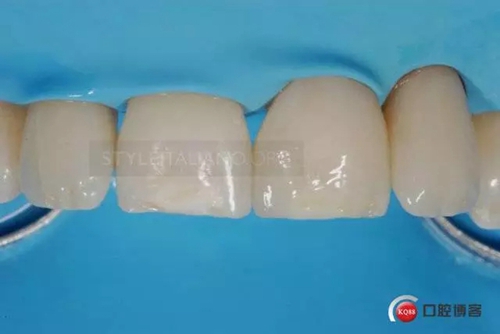

Despite having experience with both ceramic and composite materials, I decided to treat this clinical case with indirect composite overlays for the cost and benefits of this materials

After about a week I bonded the composite overlays one by one under the dam. First step was to perfectly clean the preparation sandblasting them with glycine powder

I removed all the composite excess before curing for 60 seconds for each side with a high power led lamp

I repeated the same steps on tooth 2.2

Until the immediate final outcome